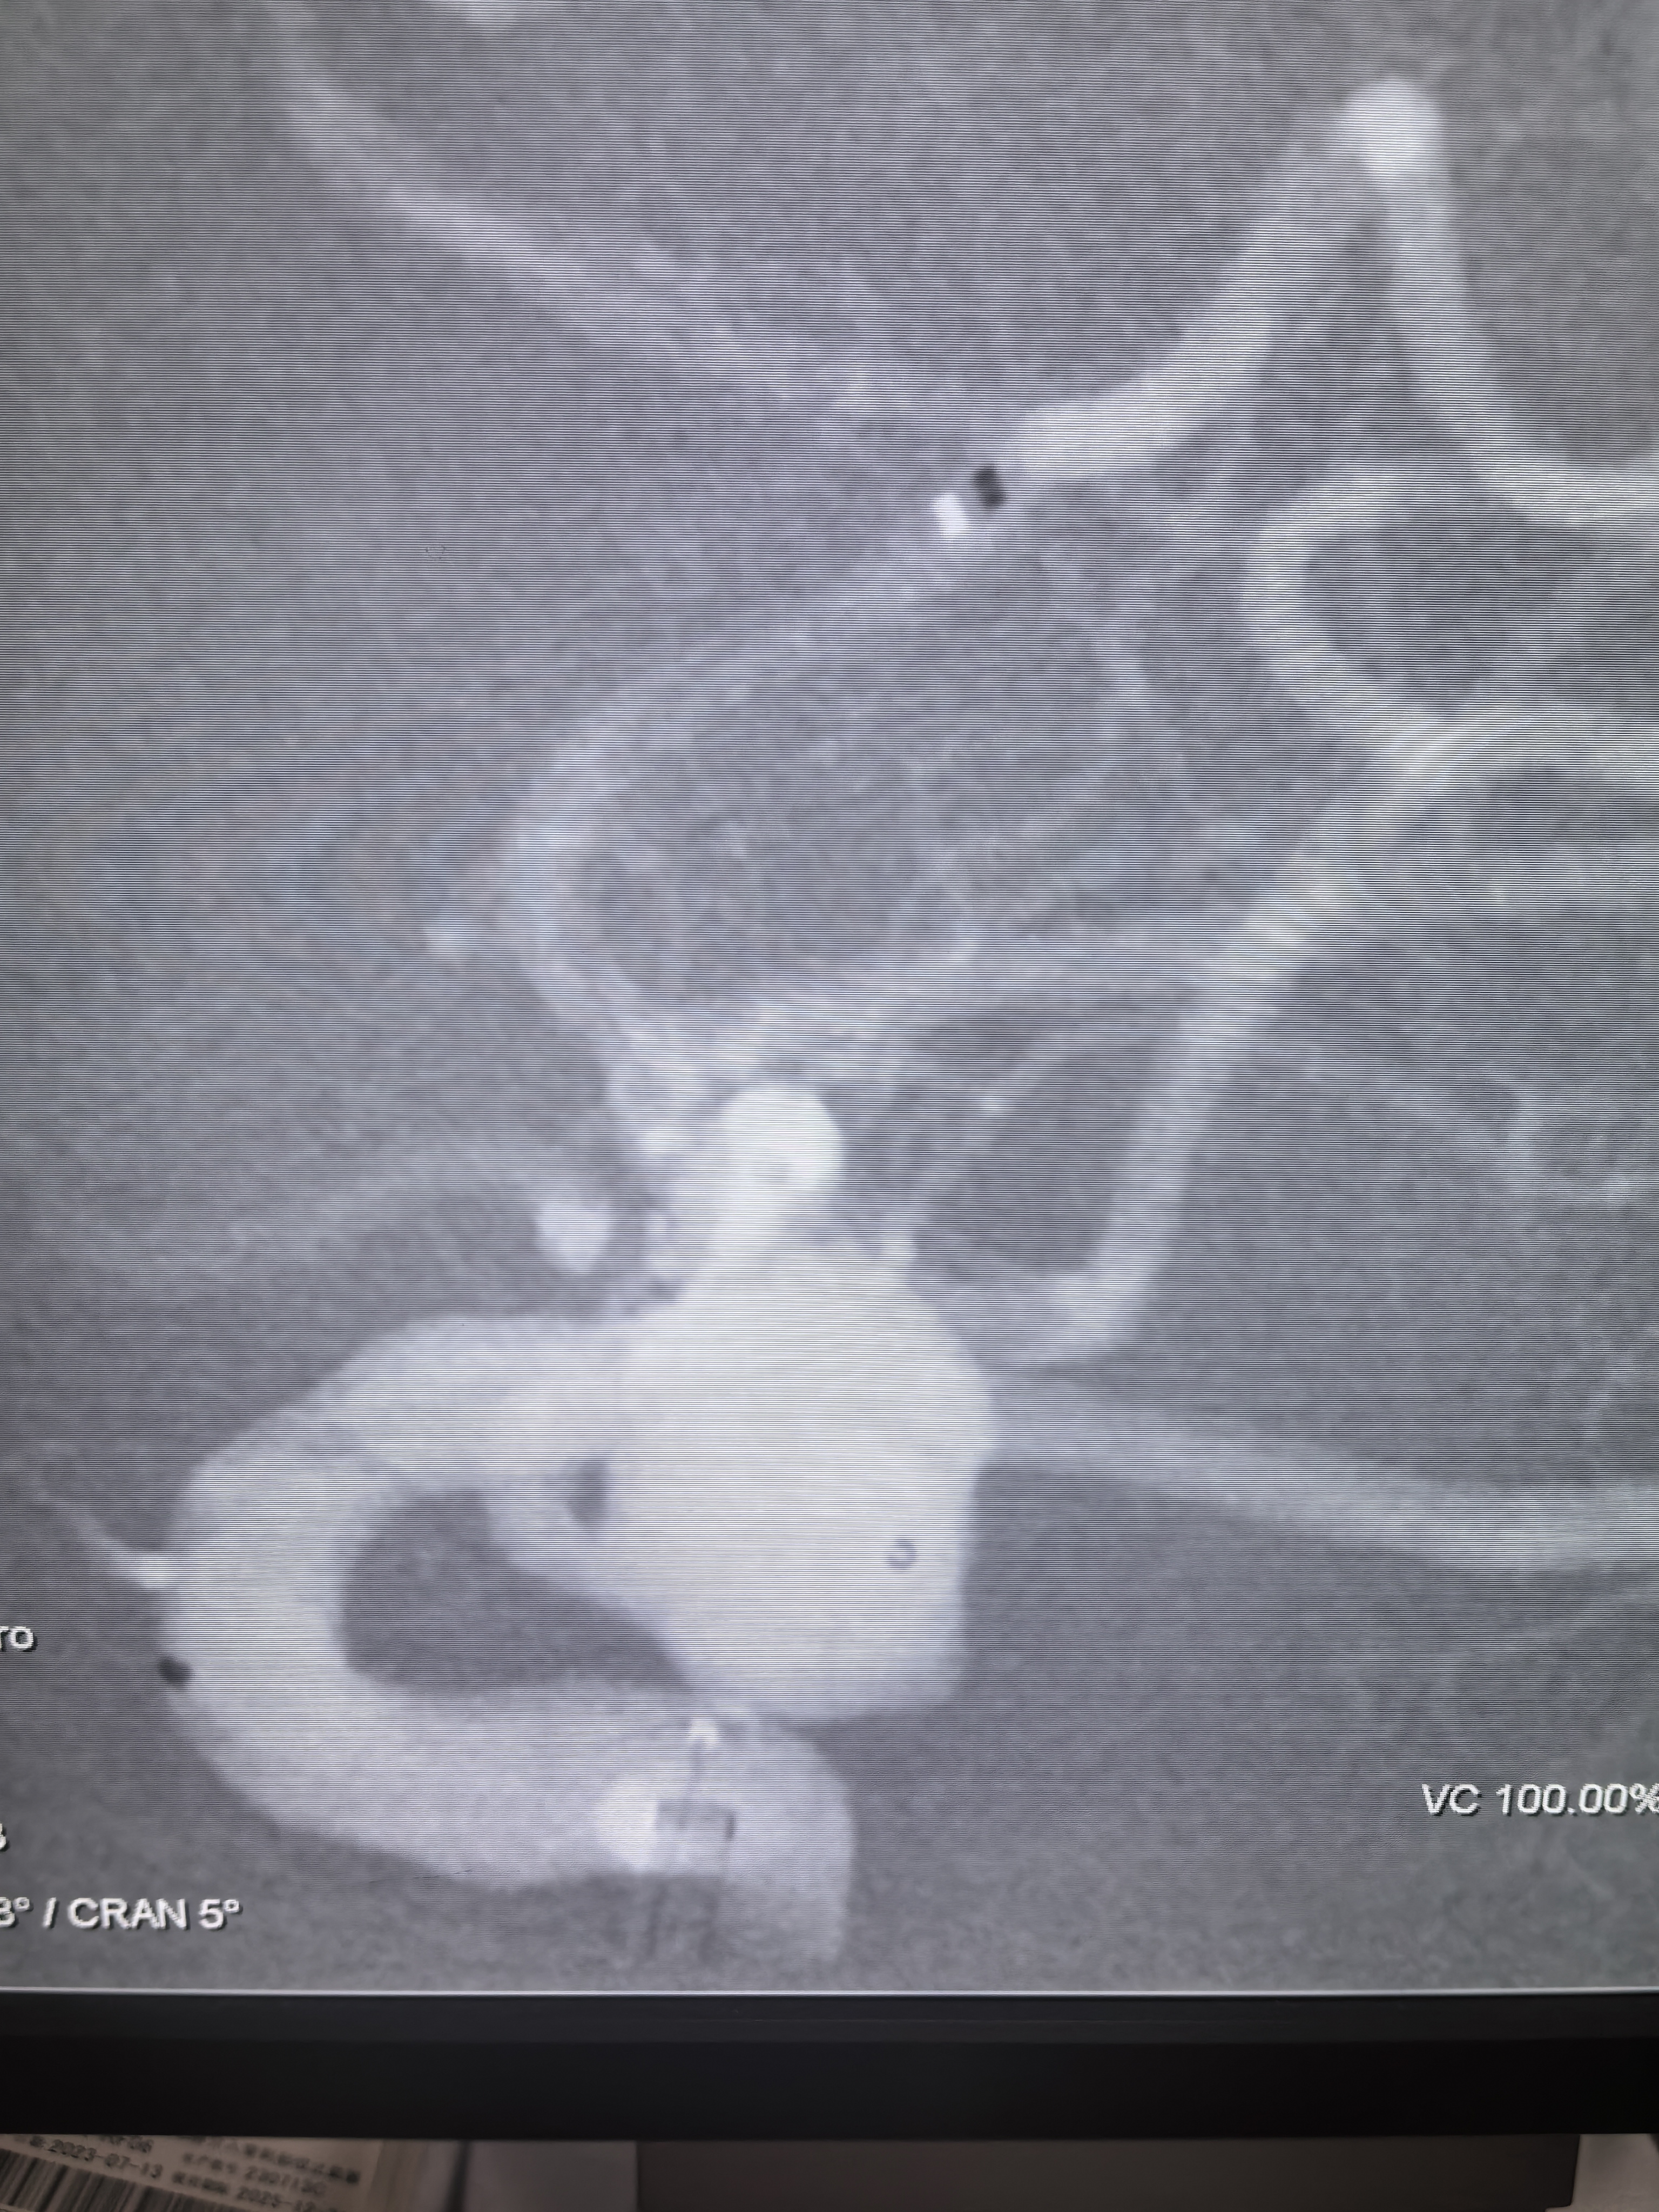

三维旋转造影!

三维重建,胚胎型大脑后动脉发自瘤体侧壁,超选困难且风险大!